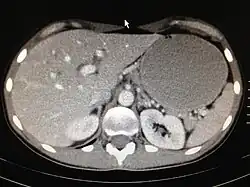

Die ergiebigste Untersuchungsmethode des Magens ist die Gastroskopie (Magenspiegelung). Bei der Magenspiegelung wird oft ein HU-Test zum Nachweis einer Helicobacter-Besiedlung entnommen. Außerdem sind gezielte Biopsien zur histologischen Untersuchung leicht möglich. Die Röntgenuntersuchung des Magens, die vor dem Aufkommen der Gastroskopie betrieben wurde, wird heute nicht mehr routinemäßig durchgeführt, da sie sehr unsichere Ergebnisse produziert. Die Ultraschalluntersuchung des Magens ist leicht möglich, liefert aber nur selten brauchbare Ergebnisse, wie zum Beispiel eine Magenausgangsstenose oder eine auffällige irreguläre Wandverdickung. Beim Ultraschall ist der Magenausgang recht gut, andere Teile wie z. B. die Cardia kaum beurteilbar. Eine Computertomographie des Magens ist ebenfalls nur in Ausnahmefällen sinnvoll. Zur Bestimmung von Helicobacter-Bakterien wird zunehmend ein Atemgastest durchgeführt.

Als Risikofaktoren des Magenkarzinoms, einer der häufigsten Krebsarten beim Menschen, sind bestimmte Ernährungsgewohnheiten, chronische Gastritis, Zigarettenrauch und Alkoholkonsum identifiziert. Das Risiko, an Magenkrebs zu erkranken, ist bei erblicher Belastung erhöht (was vermutlich mit der erblichen Übertragung des Bakteriums Helicobacter pylori zusammenhängt) – es besteht ein 3,7fach erhöhtes Risiko für Verwandte ersten Grades. Menschen mit der Blutgruppe A sind häufiger betroffen. Die Ursache ist unbekannt. Die Therapie des Magenkarzinoms erfolgt zurzeit hauptsächlich operativ,[1] etwa mittels Gastrektomie.